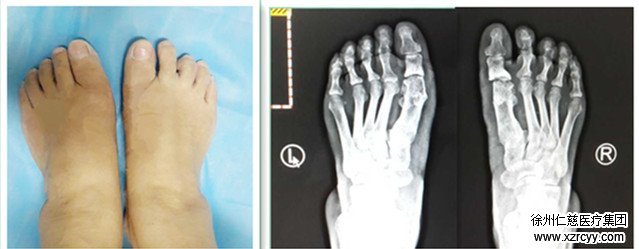

拇外翻畸形外观 拇外翻术前X线片

拇外翻畸形术后外观 拇外翻畸形术后X线片